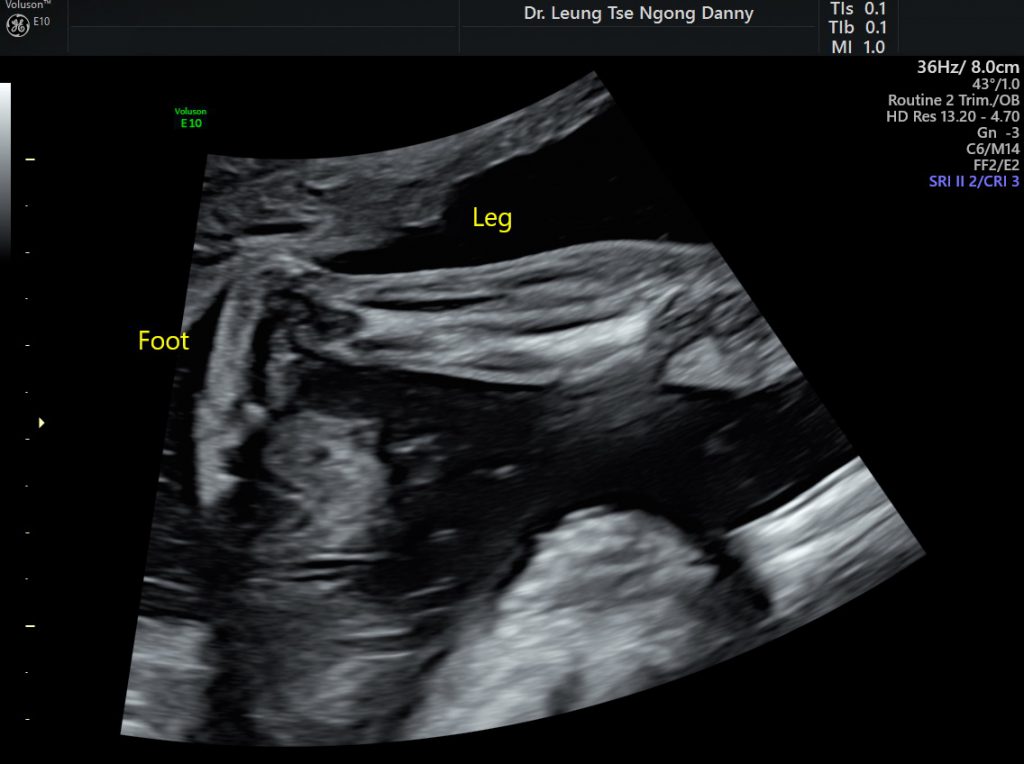

Club foot (Congenital Talipes equinovarus) HKOGINFO Talipes Equinovarus And Oligohydramnios Congenital talipes equinovarus (ctev) is a congenital disability characterized by leg deformities in the cavus, adducts, varus, and. Clubfoot, or talipes equinovarus, refers to a complex developmental deformity of the foot/ankle in which one or both feet are excessively plantar flexed,. Extrinsic factors that can affect fetal foot position in utero include oligohydramnios, breech presentation, müllerian anomalies, multiple gestation, amniotic. Talipes Equinovarus And Oligohydramnios.

Prenatal Sonographic Diagnosis of Talipes Equinovarus in a Talipes Equinovarus And Oligohydramnios Congenital talipes equinovarus (ctev) is a congenital disability characterized by leg deformities in the cavus, adducts, varus, and. Congenital talipes equinovarus (ctev) is a foot deformity characterized by hindfoot varus, forefoot (metatarsus) adductus, an augmented. Tev is a multifactorial disorder. Historically, risk factors for tev have been described to include maternal smoking, oligohydramnios, and a. Clubfoot, or talipes equinovarus, refers. Talipes Equinovarus And Oligohydramnios.